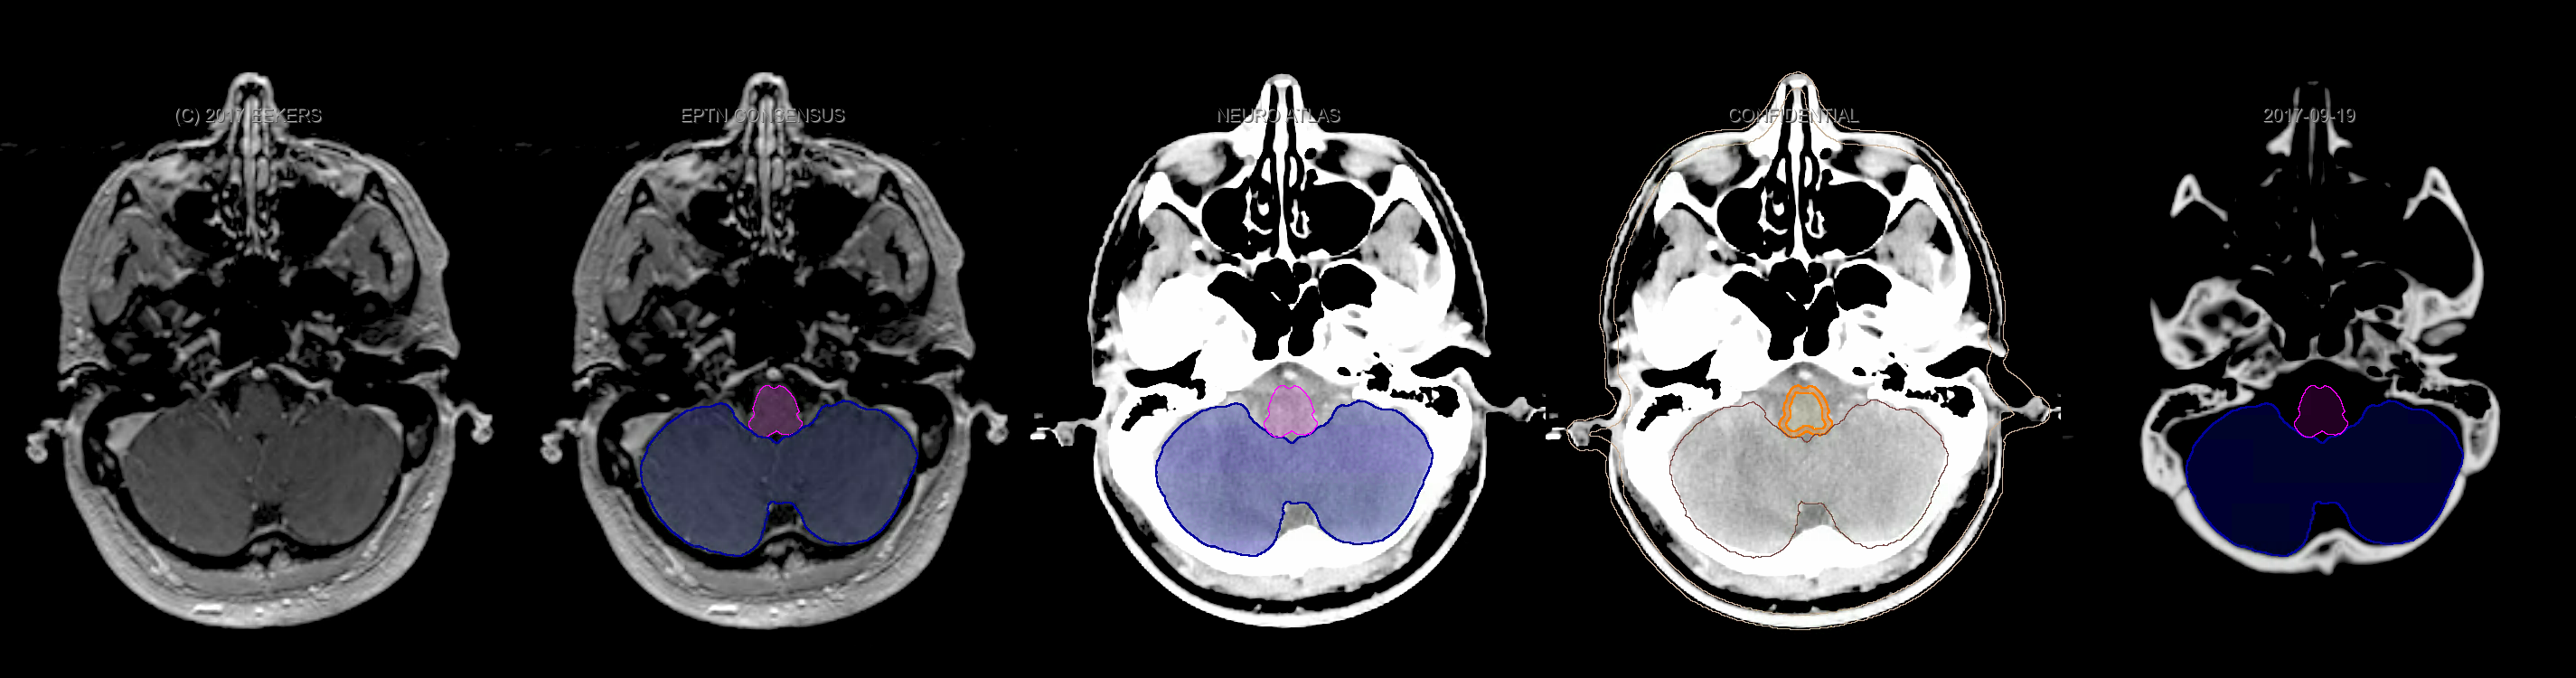

Eekers et al. have published an international neurological atlas for contouring of organs at risk in consensus with the European Particle Therapy Network (EPTN). The purpose of this consensus atlas is to decrease inter- and intra-observer variability in delineating OARs relevant for neuro-oncology. We propose this atlas is used in photon and particle therapy in order to derive consistent dosimetric data. When required this atlas will be updated according to new insights.

Included are all OARs known to be relevant for radiation-induced toxicity in neuro-oncology: brain, brainstem, cochlea, vestibulum & semicircular canals, cornea, lens, retina, lacrimal gland, optic nerve, chiasm, pituitary, hippocampus and skin. A new OAR relevant for neuro-cognition, the posterior cerebellum is also included.

Three-dimensional delineation of the fifteen consensus OARs for neuro-oncology are shown on CT and 3 Tesla (3T) MR images (slice thickness 1 mm with intravenous contrast agent). All are presented in transversal, sagittal and coronal view.

From left to right: MR without structures, MR with structures, CT (WW/WL 120/40) with structures, CT (WW/WL 120/40) with Brain and Brainstem Surface, CT (WW/WL 1500/120)with structures